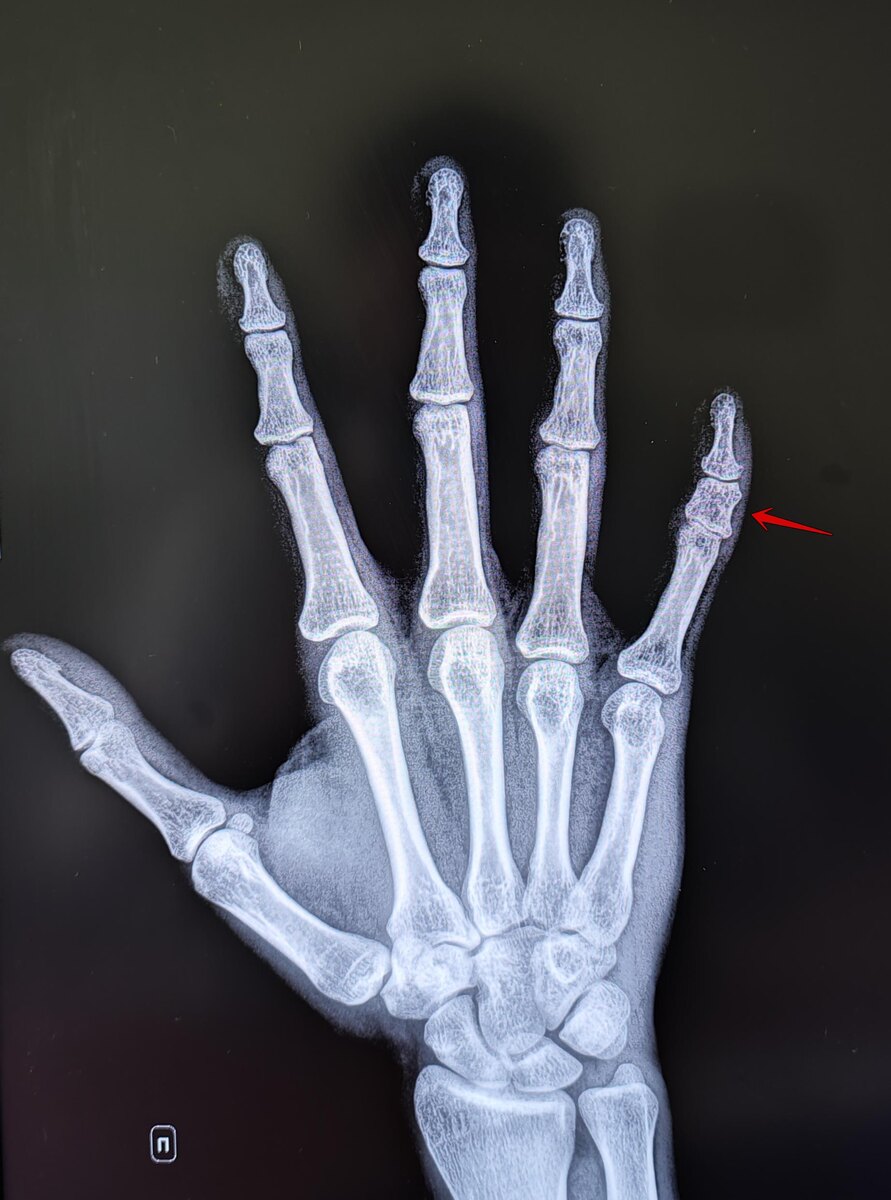

Это врождённая аномалия развития, характеризующаяся укорочением пальцев кистей и/или стоп из-за недоразвития или отсутствия фаланг. На Р-граммах правой кисти в 2х проекциях: травматических, деструктивных изменений не выявлено. Структура костной ткани не изменена. Средняя фаланга пятого пальца укорочена, утолщена. По остальным отделам кисти-без явной костной патологии. Заключение: Врожденная аномалия развития правой кисти- брахидактилия (брахифалангия) средней фаланги пятого пальца правой кисти. Категория годности с данным диагнозом по ст.67(Отсутствие, деформации, дефекты кисти и пальцев), г) при наличии объективных данных без нарушения функций-Б3(годен к в/сл с незначительными ограничениями). https://t.me/MME_SurgeryRadiolodgy https://vk.com/club223629464

Это врождённая аномалия развития, характеризующаяся укорочением пальцев кистей и/или стоп из-за недоразвития или отсутствия фаланг.

На Р-граммах правой кисти в 2х проекциях: травматических, деструктивных изменений не выявлено. Структура костной ткани не изменена. Средняя фаланга пятого пальца укорочена, утолщена. По остальным отделам кисти-без явной костной патологии.

Заключение: Врожденная аномалия развития правой кисти- брахидактилия (брахифалангия) средней фаланги пятого пальца правой кисти.

Категория годности с данным диагнозом по ст.67(Отсутствие, деформации, дефекты кисти и пальцев), г) при наличии объективных данных без нарушения функций-Б3(годен к в/сл с незначительными ограничениями).